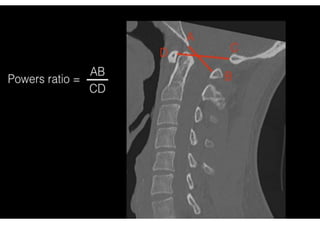

Atlanto-occipital dissociation injuries are severe and include both

1. Basion-dens interval (BDI) >10 mm in adults

2. Basion-axial interval (BAI) >12 mm in adults

3. Powers ratio >1 (insensitive to a vertical distraction injury or

posterior dissociation)

4. Atlantodental interval (ADI)

Atlanto-occipital dissociation injuriesare severe and include both atlanto-occipital dislocations and atlanto-occipital subluxations. The key to the diagnosis, in addition to visualising gross disruption of the normal alignment of the atlanto-occipital joint, hinges on using a number of lines. 1. Basion-dens interval (BDI) >10 mm in adults 2. Basion-axial interval (BAI) >12 mm in adults 3. Powers ratio >1 (insensitive to a vertical distraction injury or posterior dissociation) 4. Atlantodental interval (ADI) >3 mm in adult males >2.5 mm in adult females